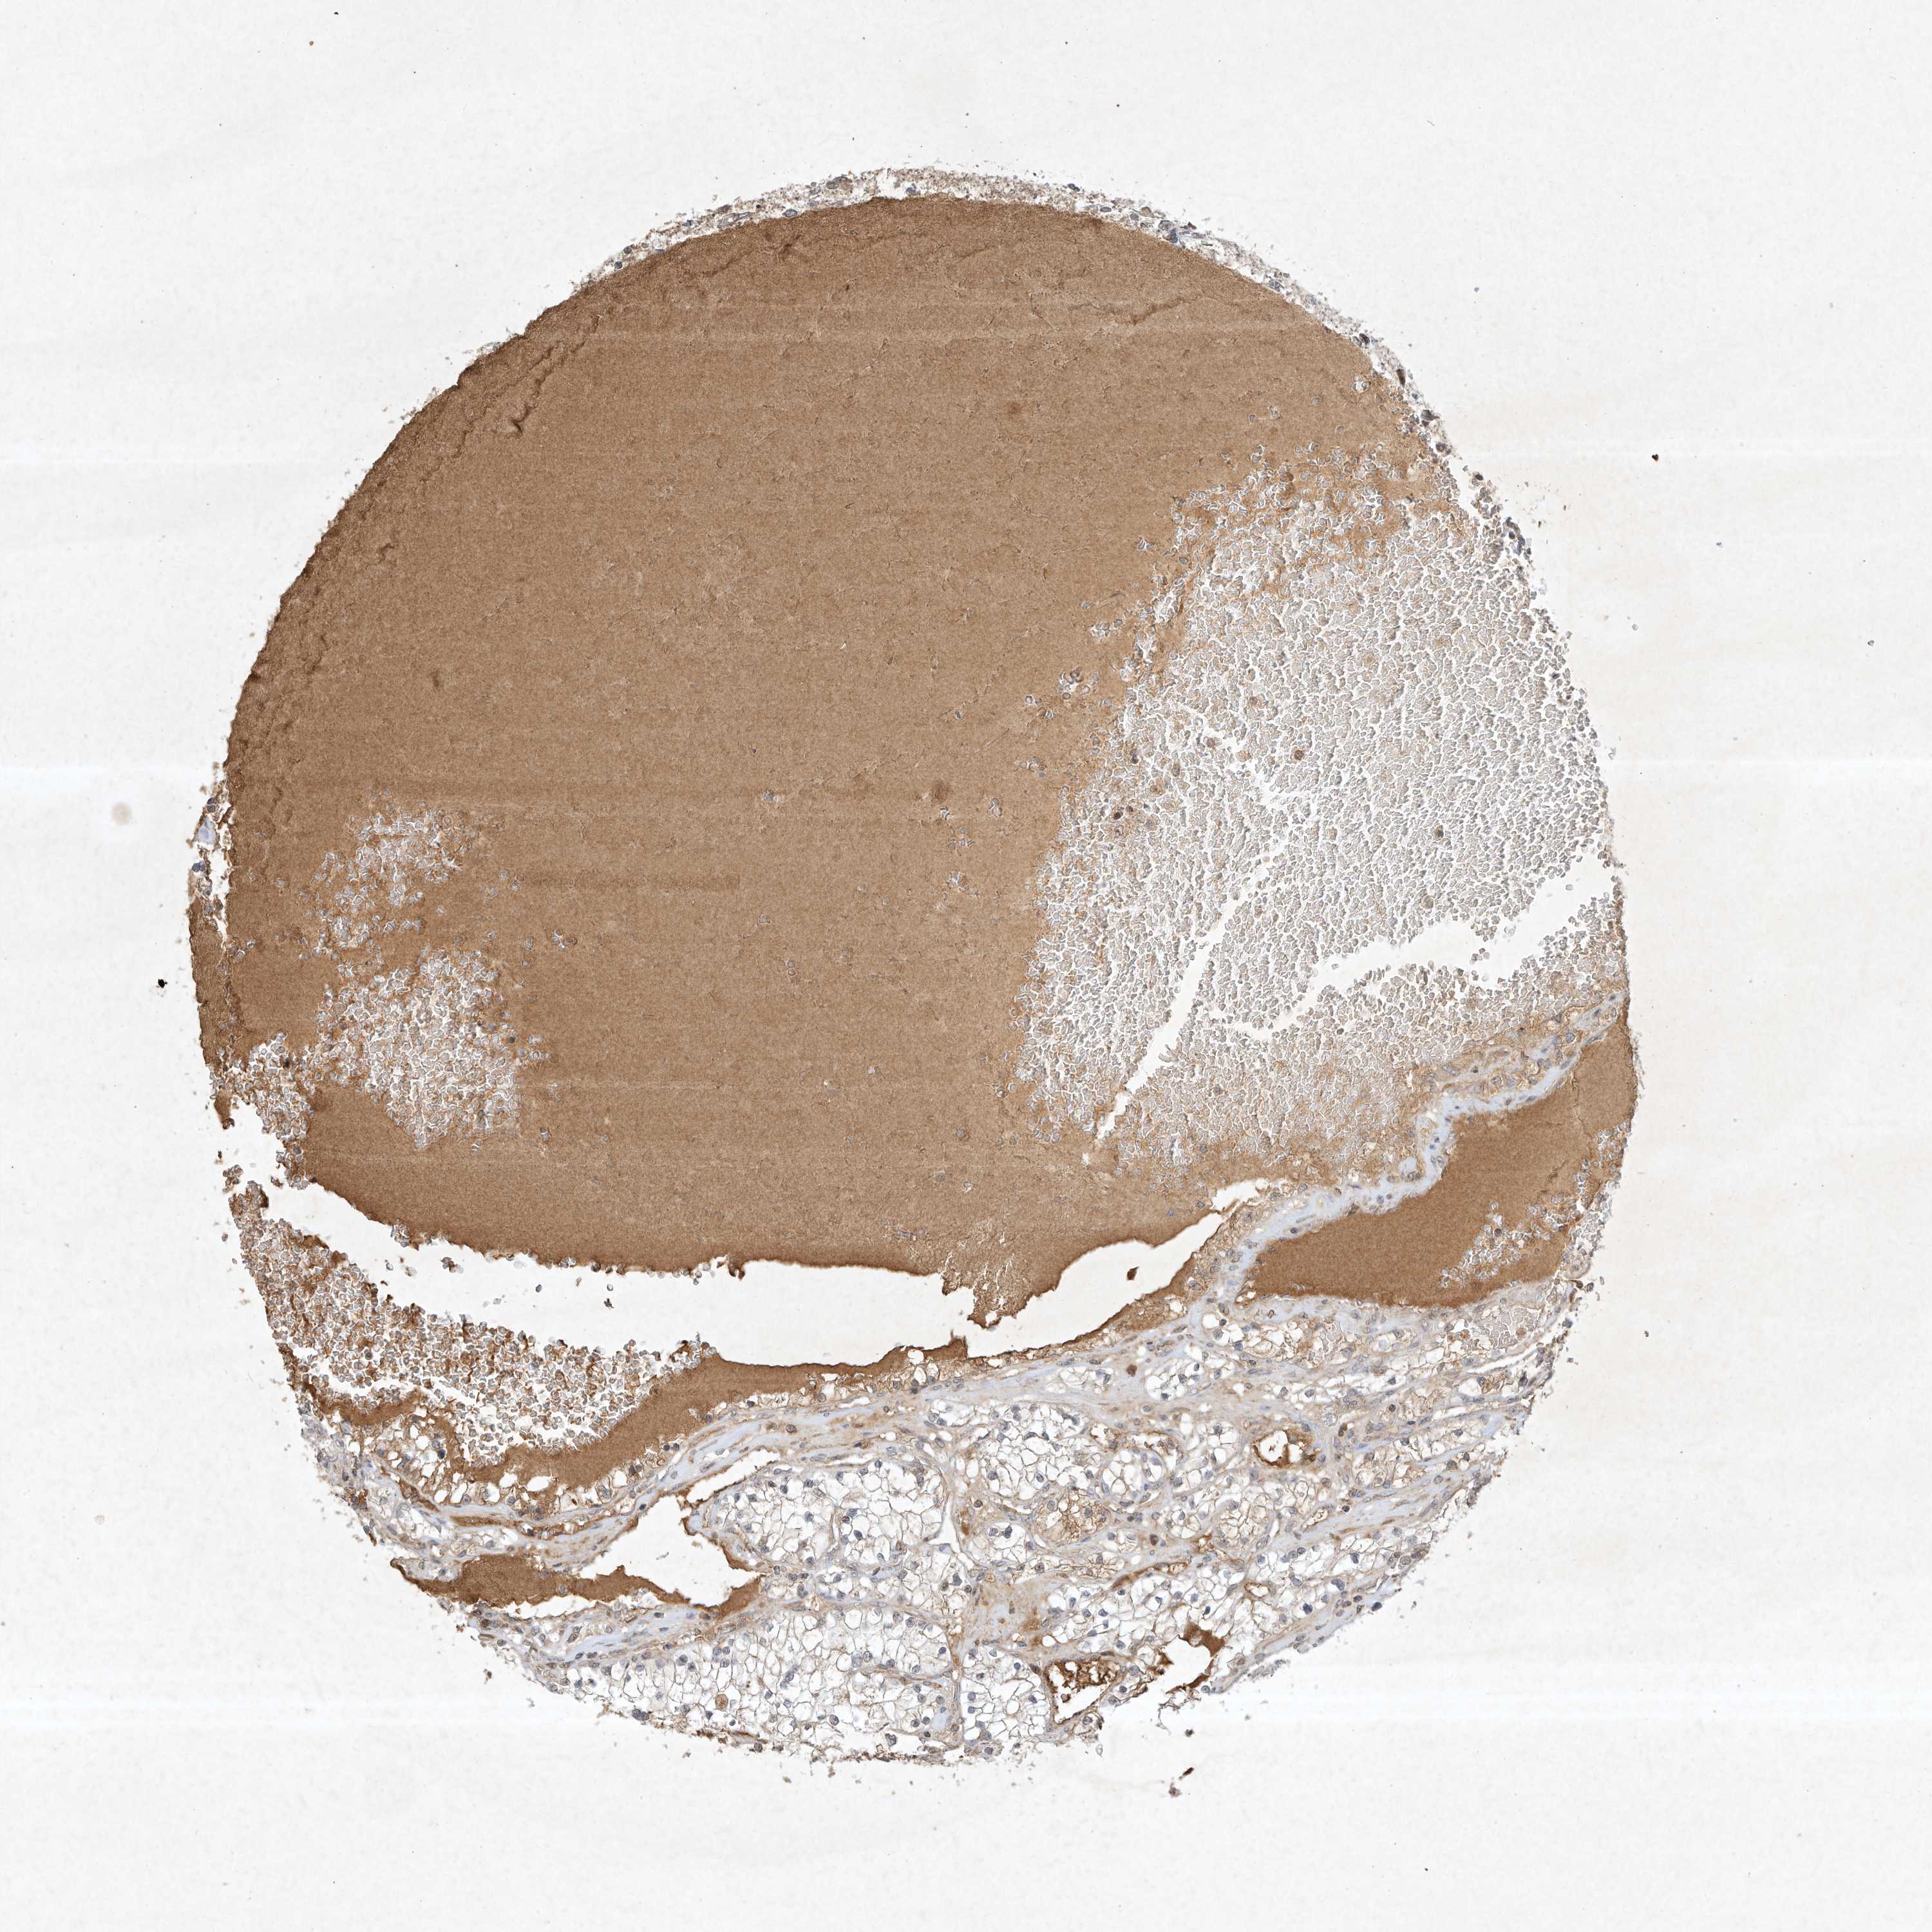

KIDNEY RENAL CLEAR CELL CARCINOMA (TCGA) - Interactive survival scatter ploti

The Survival Scatter plot shows the clinical status (i.e. dead or alive) for all individuals in the patient cohort, based on the same data that underlies the corresponding Kaplan-Meier plots. Patients that are alive at last time for follow-up are shown in blue and patients who have died during the study are shown in red.

The x-axis shows the expression levels (FPKM) of the investigated gene in the tumor tissue at the time of diagnosis. The y-axis shows the follow-up time after diagnosis (years). Both axes are complimented with kernel density curves demonstrating the data density over the axes. The top density plot shows the expression levels (FPKM) distribution among dead (red) and alive patients (blue). The right density plot shows the data density of the survived years of dead patients with high and low expression levels respectively, stratified using the cutoff indicated by the vertical dashed line through the Survival Scatter plot. This cutoff is automatically defined based on the FPKM cutoff that minimizes the p-score. The cutoff can be changed by dragging the vertical line or by entering a cutoff value in the square labeled "Current cut-off".

Under the Survival Scatter plot the p-score landscape (black curve; left axis) is shown together with dead median separation (red curve; right axis). Dead median separation is the difference in median mRNA expression between patients who have died with high and low expression, respectively. It is calculated as follows: median FPKM expression of dead patients with high expression - median FPKM expression of dead patients with low expression. This is intended to aid the user in visually exploring custom cutoffs and the associated p-scores and dead median separation.

Individual patient data is displayed and can be filtered by clicking on one or more of the category buttons on the top of the page. Categories describing expression level and patient information include: high, low, alive, dead, female, male and tumor stages. The scale of the x-axis can be toggled between linear and log-scale by clicking on the "x log" button. Mouse-over function shows TCGA ID, patient information and mRNA expression (FPKM) for each patient.

& Survival analysisi

Kaplan-Meier plots summarize results from analysis of correlation between mRNA expression level and patient survival. Patients were divided based on level of expression into one of the two groups "low" (under cut off) or "high" (over cut off). X-axis shows time for survival (years) and y-axis shows the probability of survival, where 1.0 corresponds to 100 percent.

BTRC is potential prognostic, high expression is favorable in Kidney Renal Clear Cell Carcinoma (TCGA)

Best expression cut offi

Based on the FPKM value of each gene, patients were classified into two groups and association between prognosis (survival) and gene expression (FPKM) was examined. The best expression cut-off refers the FPKM value that yields maximal difference with regard to survival between the two groups at the lowest log-rank P-value. Best expression cut-off was selected based on survival analysis .

When clicking on this number, the vertical dashed line indicating cut-off, the interactive survival plot, and the Kaplan-Meier curve will be adjusted to show results based on the best expression cut-off.

: 6.72

TCGA RNA samplesi

RNA-seq data is reported as average FPKM (number Fragments Per Kilobase of exon per Million reads), generated by the The Cancer Genome Atlas (TCGA) .

Normal distribution across the dataset is visualized with box plots, shown as median and 25th and 75th percentiles. Points are displayed as outliers if they are above or below 1.5 times the interquartile range. FPKM values of the individual samples are presented next to the box plot.

Average pTPM 5.8

Number of samples 521